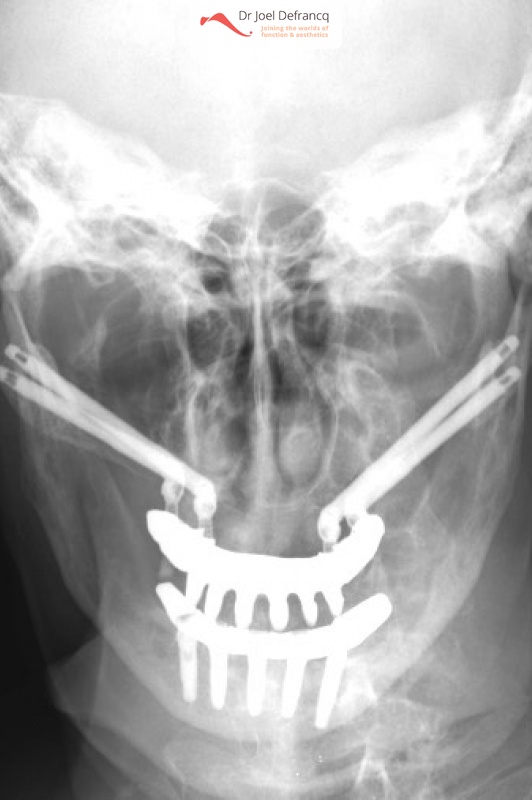

Paula: Dentale implantaten boven en onder / onmiddelijke belasting / Dentale zygoma implantaten

Behandeling tandheelkundige implantaten

- Vaste tanden op implantaten (bovenkaak)

- Vaste tanden op implantaten (onderkaak)

- Zygoma implantaten